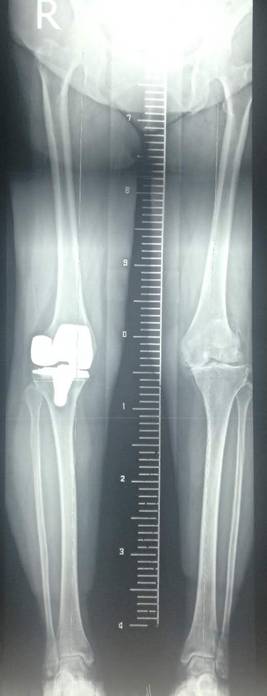

全膝表面置换术治疗重度骨关节病

优点:疗效可靠,膝关节病的最终解决方案。

单髁置换术治疗单间室骨关节病

优点:损伤小、康复快、可早期下床。

术前术后对比

全膝关节翻修术

全髋关节翻修术